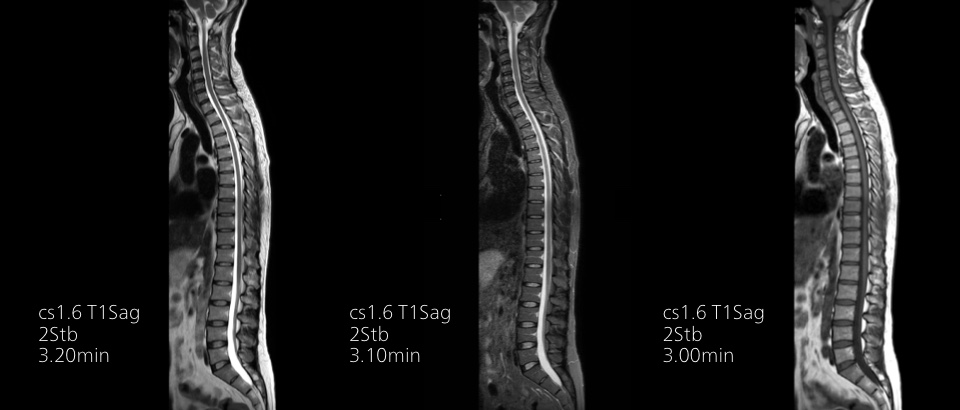

Fast exams

Ultra-fast exams

Speed MR scans by up to 50%2 with virtually equal image quality. Complete routine exams in just 5 minutes.

Turn images into answers – 50% faster

Put time on your side with Compressed SENSE to reduce scan time up to 50%2 with virtually equal image quality. Create exceptional MR images with 60% higher resolution for confident diagnosis.